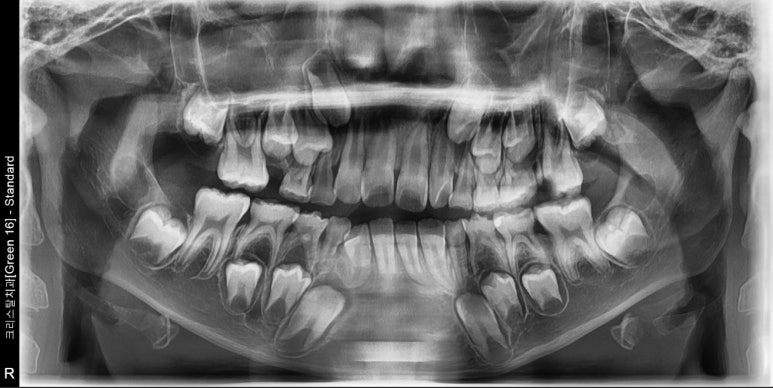

#15의 맹출 공간이 부족하여 내원한 9세 남아 입니다. 빠르게 1차교정을 마무리 했습니다.

1차교정은 6-9개월 안에 cc만 해결하고 가급적 빨리 마무리하는 것이 최선입니다.

어치피 나머지 영구치가 맹출하고 나면 또 삐뚠 치아들이 나타나는 경우가 대부분이라

5-6학년 때 2차교정이 필요한 경우가 대부분입니다. 그래서 1차라는 표현이 들어가 있는 것이죠^^

1차교정이 길어지면 아이도 지치고, 특히 부모도 지치게 되는데 나중에 또 2차교정을 하려고 하면

진짜 본 게임에서 모두 지쳐서 진행이 쉽지 않아지기 때문입니다.